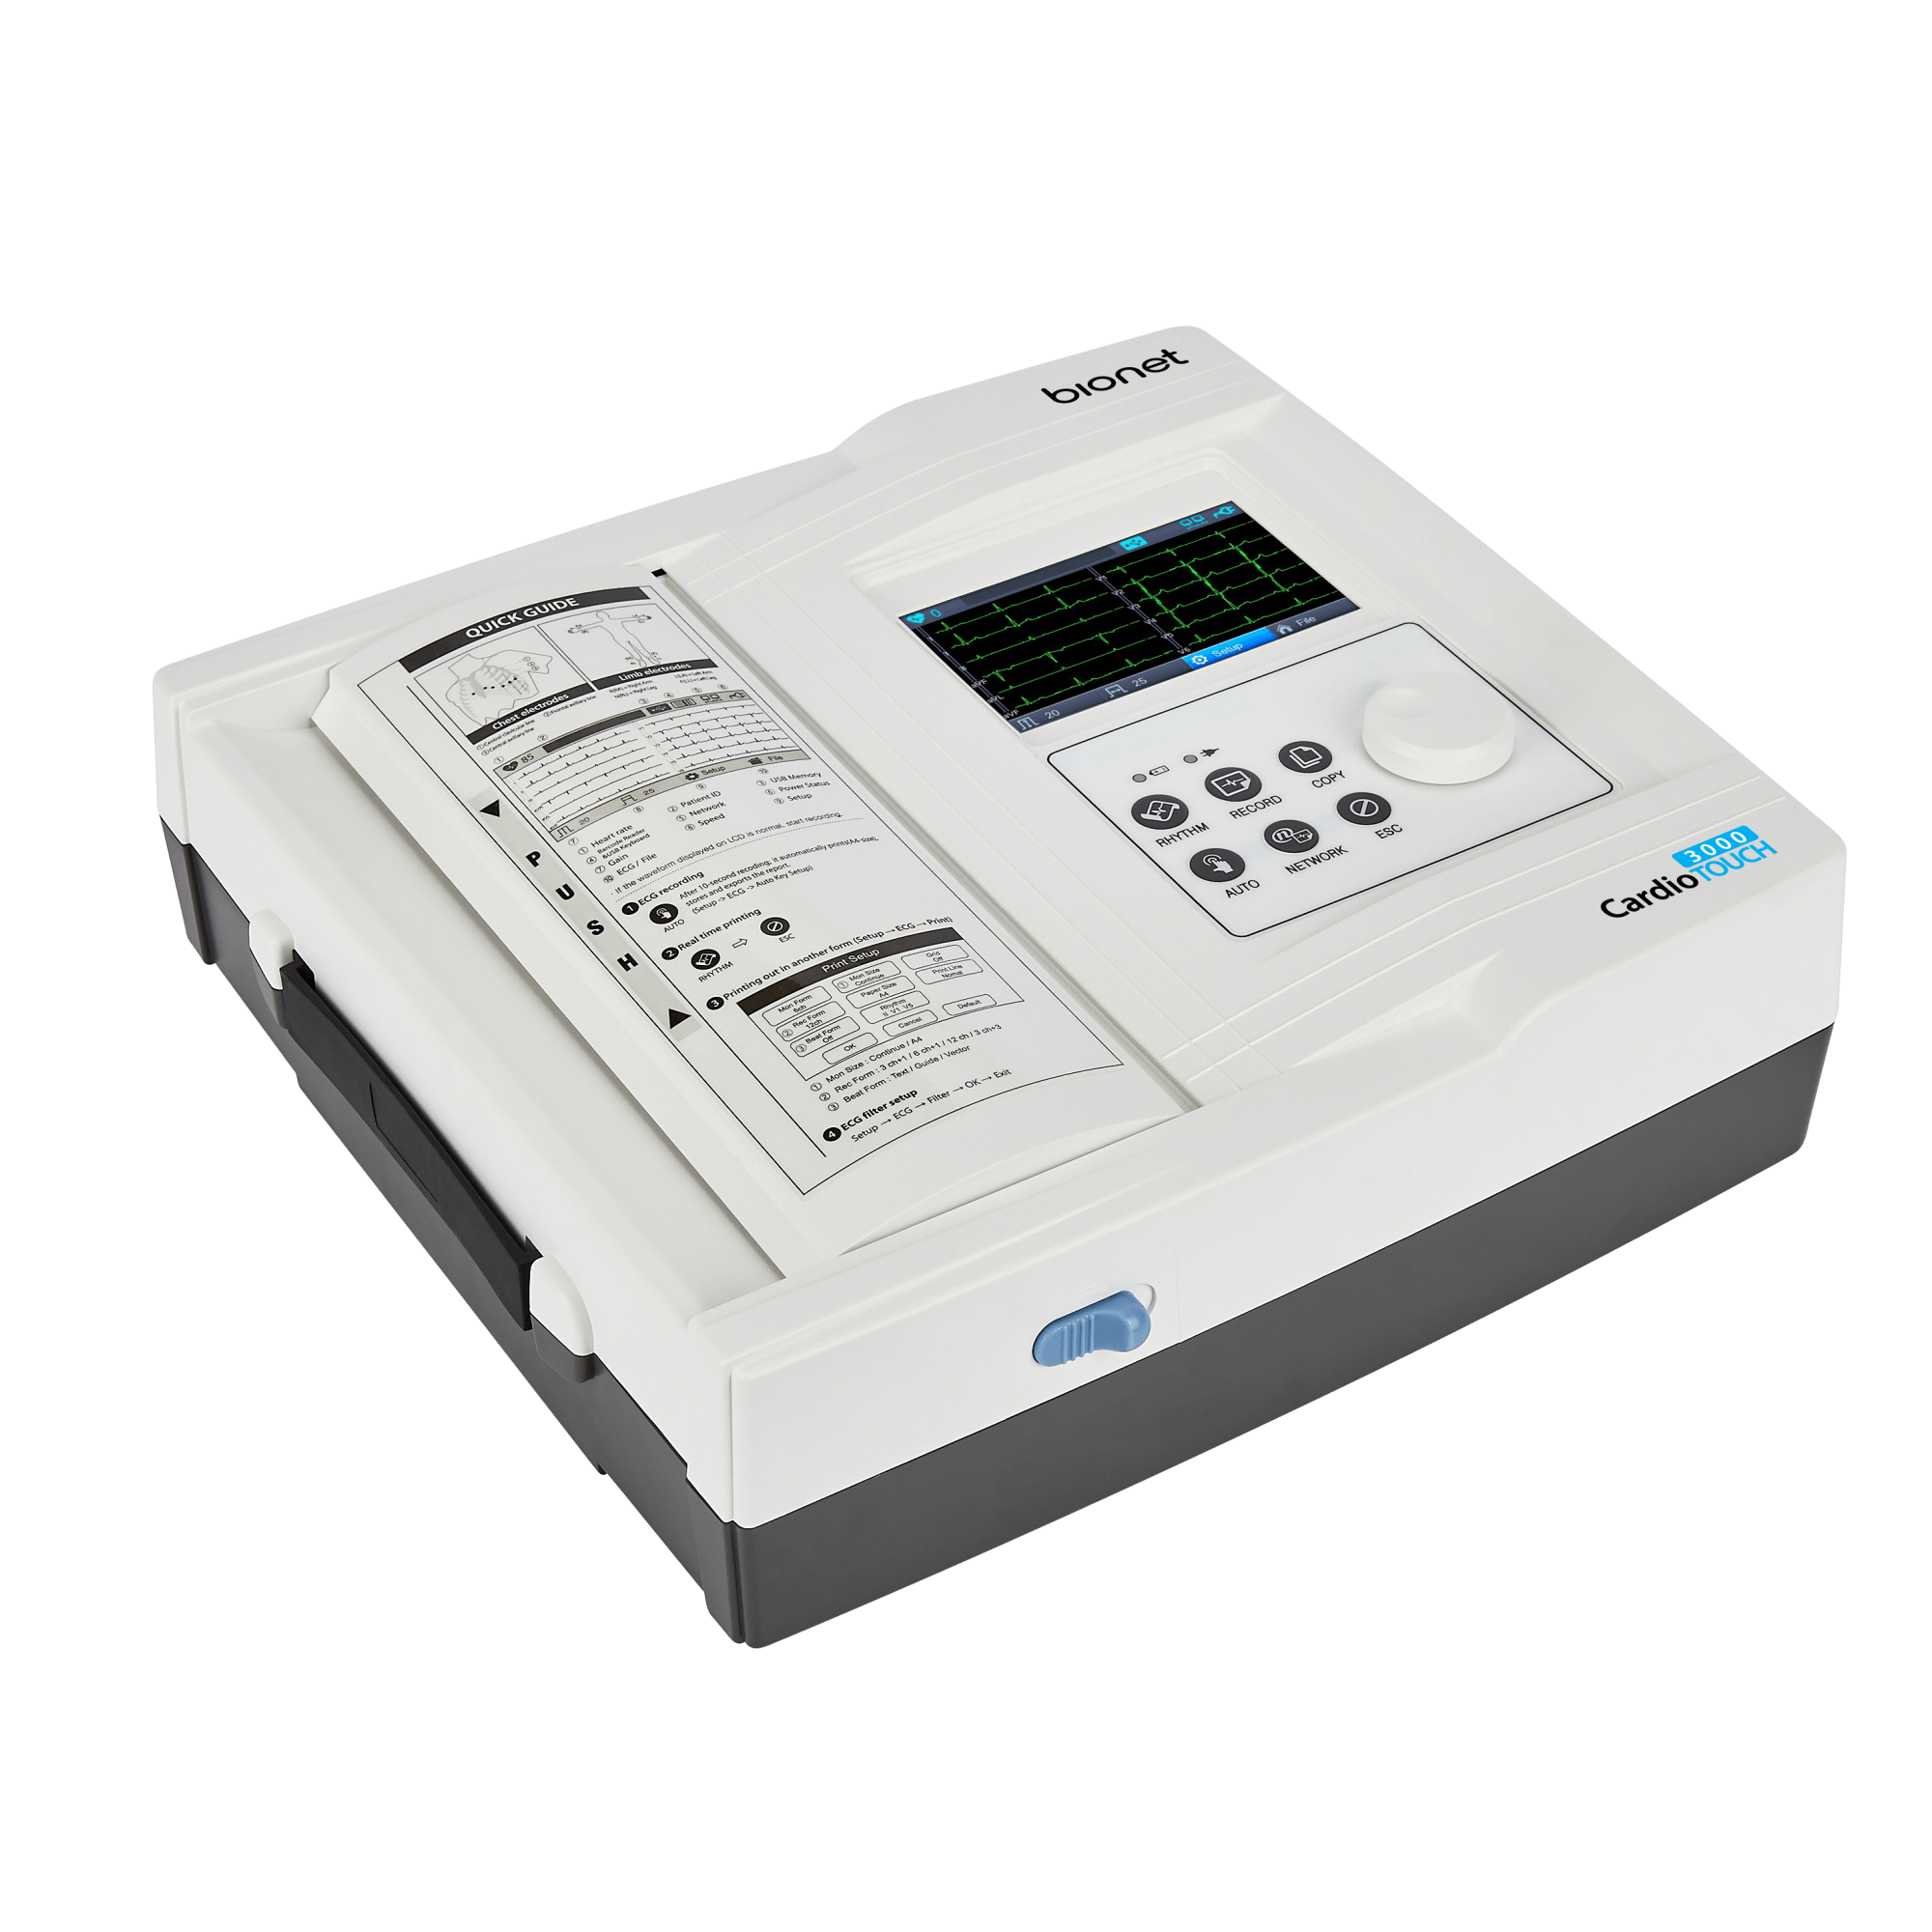

Bionet CardioTouch 3000 12 Channel ECG Machine

Bionet CardioTouch 3000 12 Channel ECG Machine